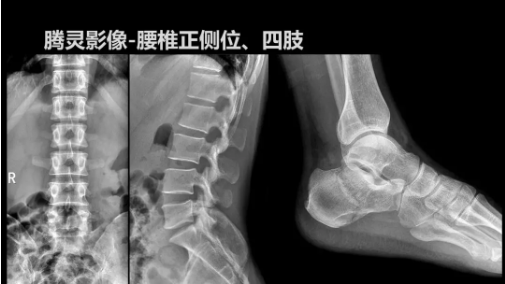

“騰靈”是安健科技的第四代動態(tài)DR產(chǎn)品,可實現(xiàn)全科室應用。如各類常規(guī)的X線檢查、消化道檢查、骨科檢查、婦科、兒科檢查等。此外,安健科技為“騰靈”在真正意義上實現(xiàn)多科室、多功能診斷進行了多項針對性設計。

相較前代產(chǎn)品,“騰靈”在圖像質(zhì)量方面得到了全面升級,“騰靈”采用17*17非晶硅平板探測器設計,采集矩陣達3072*3072,動態(tài)范圍達16bit,為成像提供超大視野的同時保證成像質(zhì)量,此外,該款機型可根據(jù)醫(yī)療機構(gòu)的差異化需求而選配不同的動態(tài)平板探測器,以此來適應不同階層用戶所需。